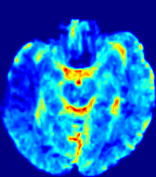

LesionRefer to captionRefer to captionRefer to captionRefer to captionRefer to captionRefer to caption𝐕rgbsubscript𝐕𝑟𝑔𝑏{\bf{V}}_{rgb}Refer to captionRefer to captionRefer to captionRefer to captionRefer to captionRefer to caption𝐕2subscriptnorm𝐕2{\|\bf{V}}\|_{2}Refer to captionRefer to captionRefer to captionRefer to captionRefer to captionRefer to captionRefer to caption3.53.53.52.82.82.82.12.12.11.41.41.40.70.70.70.00.00.0(mm/s)𝑚𝑚𝑠(mm/s)D𝐷DRefer to captionRefer to captionRefer to captionRefer to captionRefer to captionRefer to captionRefer to caption0.0200.0200.0200.0160.0160.0160.0120.0120.0120.0080.0080.0080.0040.0040.0040.0000.0000.000(mm2/s)𝑚superscript𝑚2𝑠(mm^{2}/s)Slice #1Slice #2Slice #3Slice #4Slice #5Slice #6

Figure 4: PIANO feature maps for another patient in the ISLES 2017 training set, where the lesion is located in the right hemisphere. Top row: segmented stroke lesion region (white) on different slices. The corresponding slices for the PIANO feature maps are shown in the following rows.

For a better insight into an estimated velocity field 𝐕𝐕{\bf{V}} and diffusion field 𝐃𝐃{\bf{D}}, we compute the following maps: (1) 𝐕rgbsubscript𝐕𝑟𝑔𝑏{\bf{V}}_{rgb}: Color-coded orientation map of 𝐕=(Vx,Vy,Vz)T𝐕superscriptsuperscript𝑉𝑥superscript𝑉𝑦superscript𝑉𝑧𝑇{\bf{V}}=(V^{x},V^{y},V^{z})^{T}, obtained by normalizing 𝐕𝐕{\bf{V}} to unit length and mapping its 3 components to red, green, blue respectively; (2) 𝐕2subscriptnorm𝐕2\|{\bf{V}}\|_{2}: 222 norm of 𝐕𝐕{\bf{V}}; (3) D𝐷D: scalar field in Eq. 5.

Fig. 3 and Fig. 4 show the PIANO feature maps estimated from two ISLES 2017 patients: all are highly consistent with the lesion in both cases. Details of the blood flow trajectories are revealed in 𝐕rgbsubscript𝐕𝑟𝑔𝑏{\bf{V}}_{rgb} by the ridged patterns and the sharp changes of colors in the unaffected (right) hemisphere, while the flat patterns appearing within the lesion provide little directional information about the velocity and indicate low velocity magnitudes. Velocity magnitudes are more directly visualized via 𝐕2subscriptnorm𝐕2\|{\bf{V}}\|_{2}, from which one can easily locate the lesion where 𝐕2subscriptnorm𝐕2\|{\bf{V}}\|_{2} is low. D𝐷D also indicates lower diffusion values in the lesion, though with less contrast potentially due to the fact that it captures the accumulated effect of CA diffusion at the voxel-level.